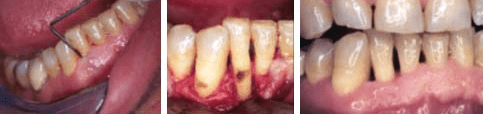

Procedimiento de cirugía periodental para eliminación de cálculo subgingiva